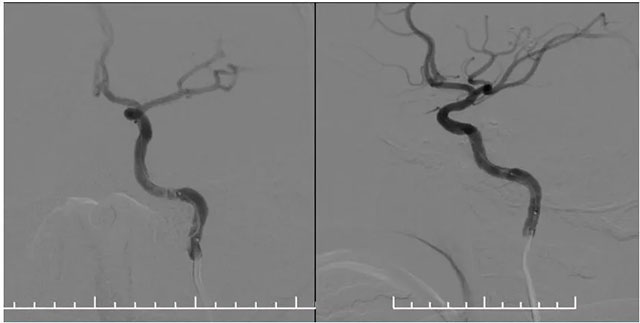

▲ 藥物洗脫球囊在微導(dǎo)絲導(dǎo)引下到位于左側(cè)椎動脈支架內(nèi),充分?jǐn)U張藥物球囊使其貼壁

▲ 球囊擴張后,支架內(nèi)狹窄明顯改善,支架貼壁良好

再次超選至左側(cè)鎖骨下動脈近椎動脈開口處,單次造影后明確開口狹窄程度,測量狹窄段長度及近遠端血管直徑,選取合適球囊。隨后在微導(dǎo)絲輔助下通過支架內(nèi)再狹窄段超選至左側(cè)椎動脈V2段,選用2.5*15球囊,沿微導(dǎo)絲到位于狹窄段,球囊擴張至8atm,再次行椎動脈造影,血流有所改善。再次將球囊下移,球囊擴張至14atm,撤除球囊后行即刻造影示血流較前通暢。選擇3.5*15藥物洗脫球囊,超選至狹窄處,予以6atm,后撤除球囊,行即刻造影示血流較前明顯改善,再次行椎動脈造影雙側(cè)大腦后動脈及基底動脈血流通暢。